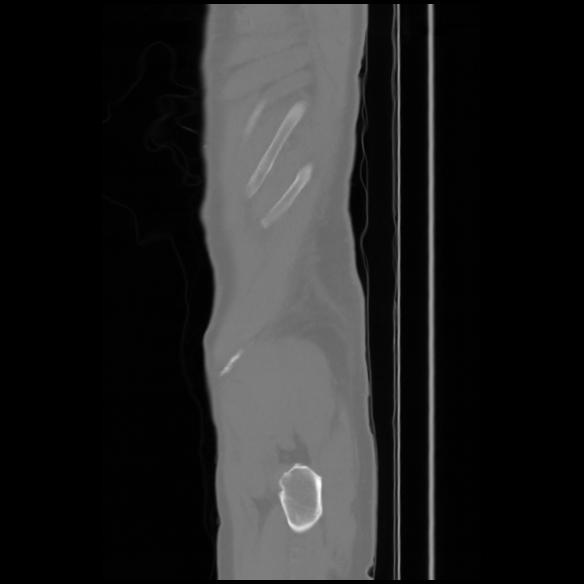

7 CUERPO,CE,Sagittal,3.000,CUERPO,Sagittal,